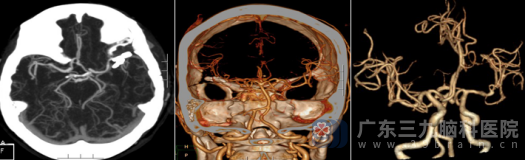

经过近八小时的精雕细琢,外十科团队成功实施了“左侧大脑中动脉巨大动脉瘤夹闭术(孤立术)+动脉瘤切除术”。术后CTA显示:局部瘤体已完全消失,周围血管通畅,大脑血供良好。